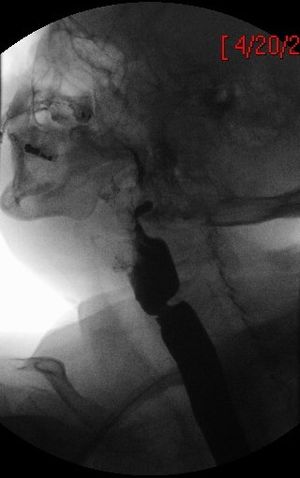

연속적인 조영 위장관 방사선 촬영이나 상부 위장관 내시경 검사를 통해 식도 웹의 존재를 확인할 수 있다.[3] 혈액 검사에서는 철 결핍성 빈혈과 일치하는 저색소성 소구성 빈혈이 일반적으로 나타난다. 영향을 받은 점막의 생검에서는 상피 위축(수축)과 다양한 정도의 점막하 만성 염증이 나타나는 것이 일반적이다. 상피 이형성증 또는 이형성증이 나타날 수도 있다. 어떤 경우에는 이 증후군이 윤상 연골 후 악성 종양으로 나타날 수 있으며, 후두 연골 마찰음의 부재로 감지할 수 있다.

바륨 식도 조영술과 비디오투시경 검사는 식도 웹(esophageal webs)을 감지하는 데 도움이 될 수 있다. 식도 위 십이지장 내시경 검사는 이러한 웹의 육안적 확인을 가능하게 하며, 이는 상피하 섬유증에 의해 발생한다.

바륨 식도 조영술과 비디오투시경 검사는 식도 웹(esophageal webs)을 감지하는 데 도움이 될 수 있다. 식도 위 십이지장 내시경 검사는 이러한 웹의 육안적 확인을 가능하게 하며, 이는 상피하 섬유증에 의해 발생한다.5. 4. 조직 검사